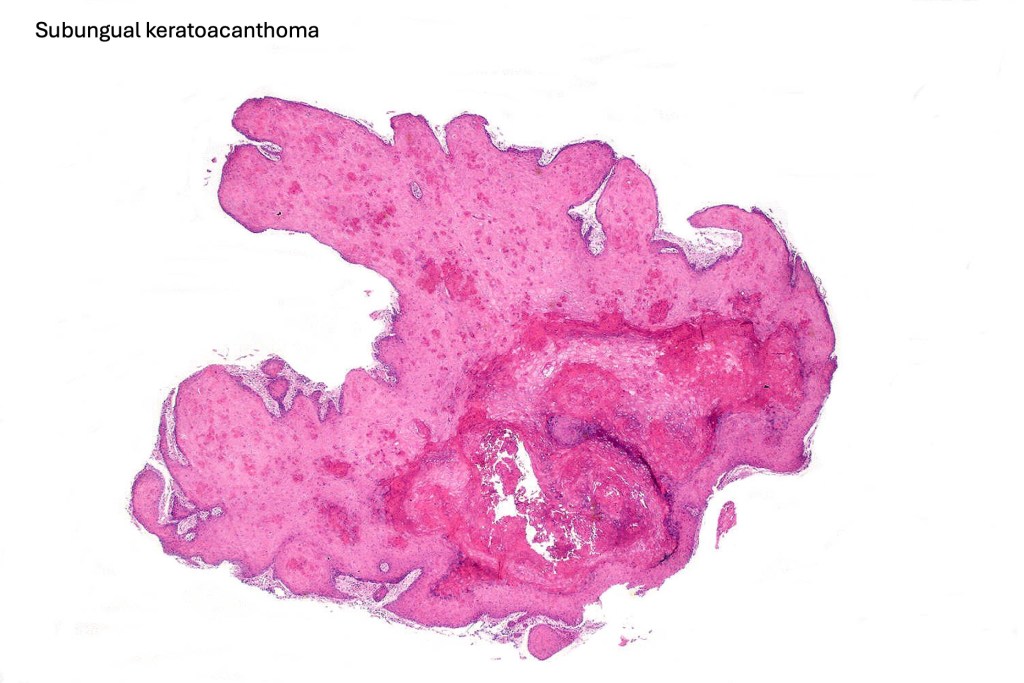

Subungual keratoacanthoma

•Derives from nail matrix

•Predilection for thumb & forefinger

•Morphologically like cutaneous lesions with ground glass cytoplasm and very conspicuous dyskeratosis

•Basal mitoses & mild cytological atypia